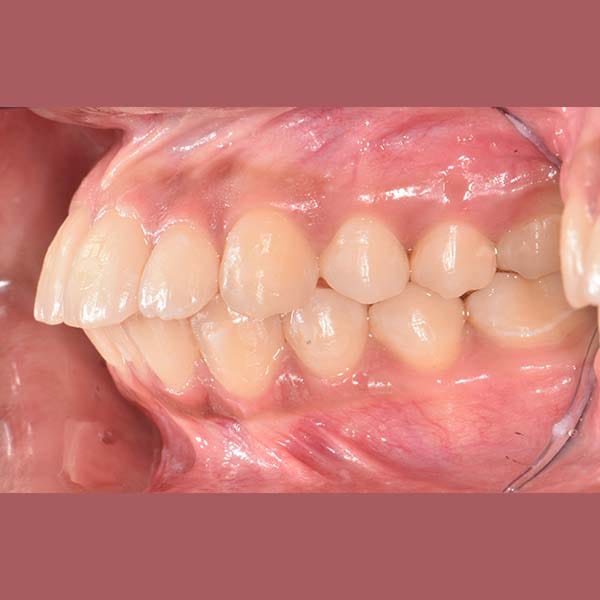

راجعتني هذه الآنسة الشابة وهي تشكو من بروز أسنانها الأمامية في كلا الفكين العلوي والسفلي، وهي حالة نسميها عادةً “البروز المضاعف”.

بعد الفحص، أكد الدكتور خالد الكاتب أن البروز كان كبيراً، وفي معظم هذه الحالات، يكون الحل الأمثل هو قلع بعض الأسنان لتوفير مسافة. وبالفعل، اعتمدت خطة العلاج على قلع الضواحك العلوية والسفلية. تم بعد ذلك استخدام تقويم الأسنان لاستغلال هذه الفراغات في إرجاع الأسنان الأمامية للخلف وتعديل ميلانها.

كما تظهر الصور، تم تصحيح البروز المضاعف بشكل كامل. تراجعت الأسنان الأمامية في كلا الفكين إلى وضعها المثالي، مما أدى إلى تحسين كبير في المظهر الجانبي للوجه وابتسامة أكثر جمالاً وتوازناً. في النهاية، بات بإمكان مراجعتنا الابتسام بثقة مجدداً.